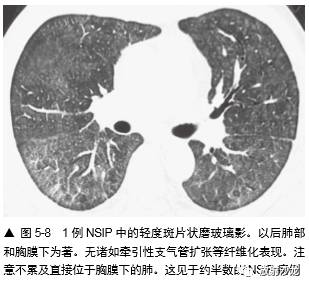

亚急性或慢性症状病例中磨玻璃影最常见的病因包括(表 5-1):间质性肺炎,如非特异性间 质性肺炎(NSIP)(图 5-8,图5-11),特发性 或其他特异性疾病,如硬皮病或其他胶原血管病,脱屑性间质性肺炎(DIP)(图 5-12) ,呼吸细支气管炎-间质性肺疾病(RB-ILD),过敏性肺炎(HP)(图 5-5,5-13), 机化性肺炎(OP),药物反应,慢 性嗜酸性肺炎(图 5-14),淋巴样间质性 肺炎(LIP),Churg-Strauss综合征, 类脂质肺炎(图5-15)和慢性或反复性吸入性肺炎,非黏液性和黏液性肺腺癌(图5-16) , 结节病,和肺泡蛋白沉着症(PAP)(图 5-17)。

因为磨玻璃影反映存在纤维化或炎症,诊断 时要小心,仅在不伴有HRCT 纤维化表现,或以 磨玻璃影为主要表现时诊断(图 5-5 ~图 5-8)。如磨玻璃影仅见于有牵引性支气管扩张或蜂窝等 HRCT 的纤维化改变的肺区内,纤维化可能将使 主要的组织学异常(图5-4,图5-9)。例如,在 Remy-Jardin 等的一项研究中,所有 HRCT 上的磨 玻璃影区内有牵引性支气管扩张或细支气管扩张 的病例,活检都有纤维化。然而,在不伴有牵引 性支气管扩张的磨玻璃影区的病例中,肺活检时 92% 发现有活动性炎症。